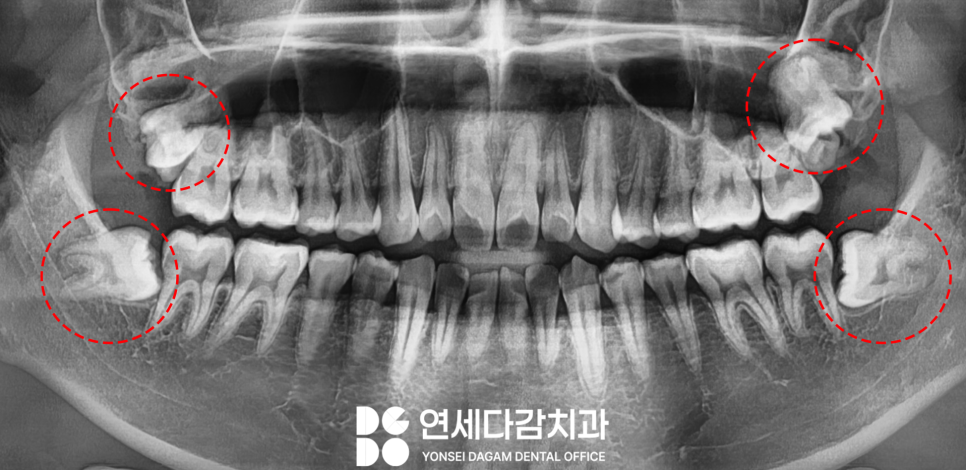

해당 케이스는 사랑니가

위 아래 모두 존재하였는데요.

위턱에 위치한 사랑니 근처에

뭔가 겹쳐 보이는 양상이

눈에 띄었습니다.

실제 구강을 살펴보면,

양쪽 모두 잇몸 밖으로

치아가 부분 맹출 된 모습을

확인할 수 있었습니다.

가락동 치과 에서는 겹쳐 보이는

구조물이 과잉치가 아닌가

의심되었는데요.